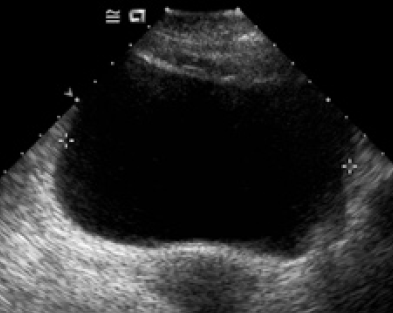

We present some cases with pneumonic adenocarcinoma. Figure 1 showed NMA type pneumonic adenocarcinoma. The consolidation with air bronchogram sign is seen in right lower lobe, and centrilobular nodules in right middle lobe. Figure 2 showed the IMA type pneumonic adenocarcinoma. The bulging fissure and consolidation with cavity or cyst are seen in right lower lobe.